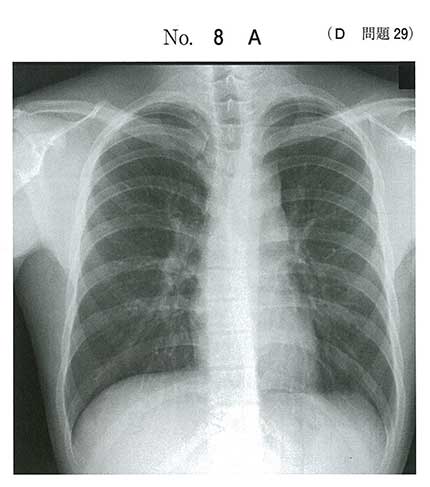

Eを測定する必要がない理由としては基本的にサルコイドーシスはBHLで、ほぼ両側性。少なくてもCTで右肺のリンパ節は腫れていないので不必要ってことかな?

eも実臨床では取りたい気がしますが、>>3,>>4にあるように、eが答えなのでしょう。たしかにあの位置はリンパ節腫脹ではなく、胸腺腫などを疑う位置ですから。

Eは画像からしてsarcoidosisのBHLの事を言ってるだろうからいい気がする。

画像が前縦隔腫瘍なので、サルコイドーシスのeにしました。

たしかに両側肺門リンパ節腫脹にも見えますが、前縦隔腫瘍を無視する必要はないと思います。